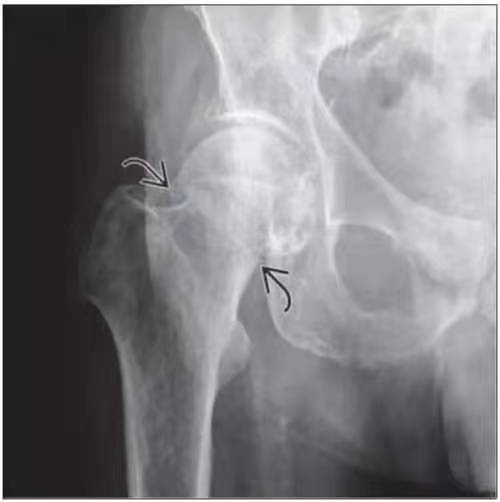

股骨颈骨折是指股骨头下至股骨颈基底部之间的骨折,主要发生于老年人,造成老年人发生骨折有两个基本因素,骨质疏松骨强度下降,加之股骨颈上区滋养血管孔密布,均可使股骨颈生物力学结构削弱,使股骨颈脆弱。另外,因老年人髋周肌群退变,反应迟钝,不能有效地抵消髋部有害应力,加之髋部受到应力较大(体重2~6倍),局部应力复杂多变,因此不需要多大的暴力,如平地滑倒、由床上跌下或下肢突然扭转,甚至在无明显外伤的情况下都可以发生骨折。而青壮年股骨颈骨折,往往由于严重损伤如车祸或高处跌落致伤。